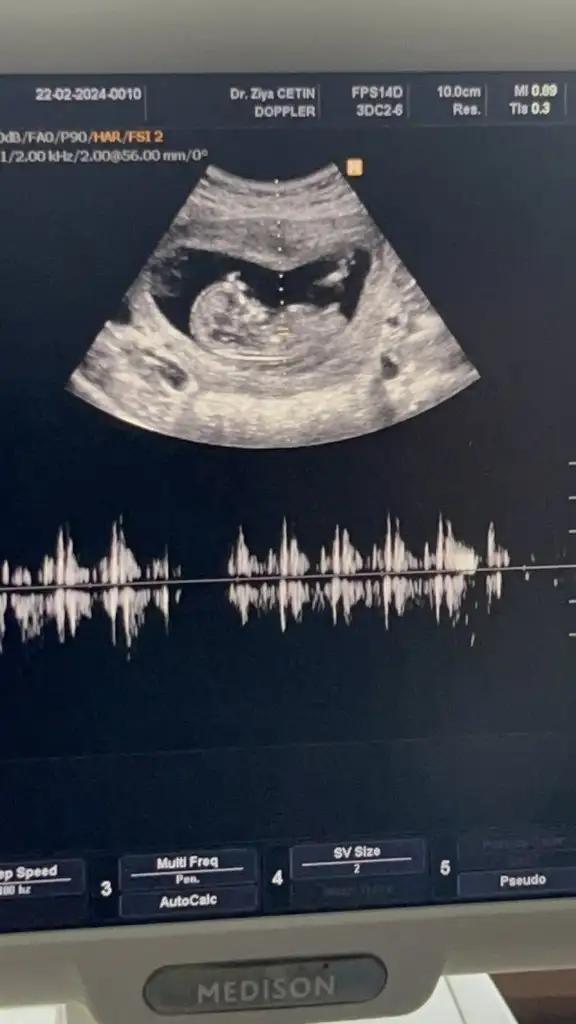

Merhaba, instagramda nereye baktırmıştınız acaba?Ben Instagram dan baktırmıştım, tahminim %70 kız demişti, dün Dr %99 erkek dedi

Merhaba canım nuba göre erkek duruyor